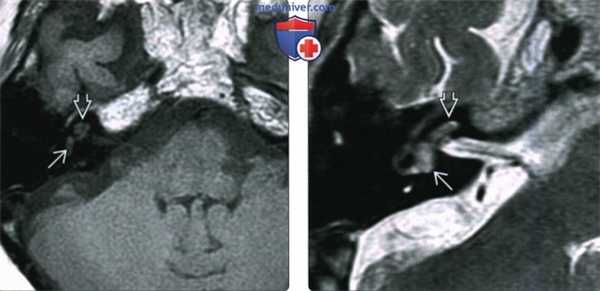

(Слева) При аксиальной МРТ Т1ВИ определяется минимальный гиперинтенсивный сигнал в преддверии и улитке у пациента с вестибулокохлеарной шванномой.

(Справа) При аксиальной MPT Т2ВИ визуализируется материал с сигналом, соответствующим мягким тканям, замещающий сигнал, типичный для нормальной жидкости в преддверии и улитке у пациента с ИЛШ вестибулокохлеарного типа. Эти опухоли чаще распознаются на МРТ высокого разрешения (Т2) в условиях высокой настороженности.